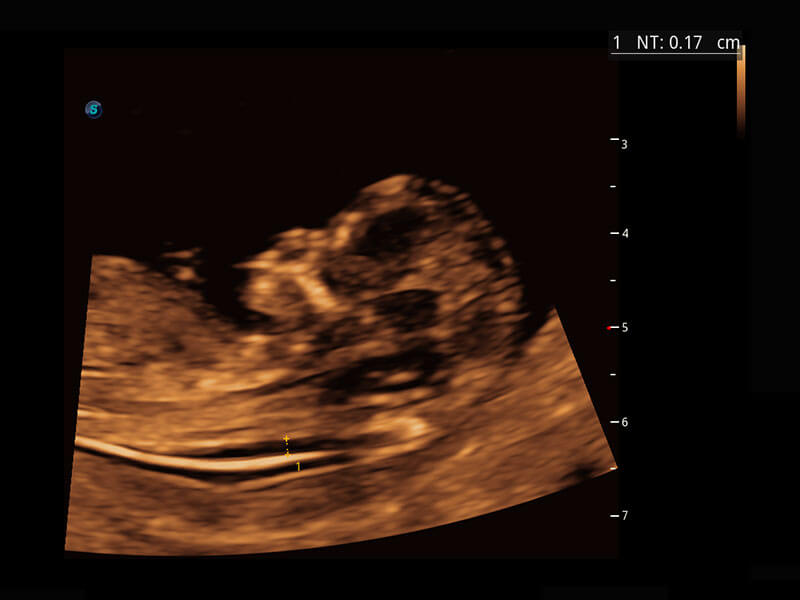

P60在胎儿早孕期超声筛查中为您带来优异的图像质量。

早孕-胎心

高分辨率容积成像-早孕胎儿

P60提供简单易学易用的高端诊断工具,为您中晚孕筛查提供快速清晰的解剖信息。

1 OFD(HC): 87.03 mm

HC: 251.00 mm

GA: 27w 1d

HC/AC: 96.13 %

2 BPD: 70.56 mm

GA: 28 w 2d

S-Fetus(acq.)

&

S-Fetus(meas.)

S-Fetus能够助您在实时扫查过程中自动识别标准切面、自动测量并录入报告。一个按键,即可快速、高效地获取胎儿生理指标,简化您的产科检查操作。